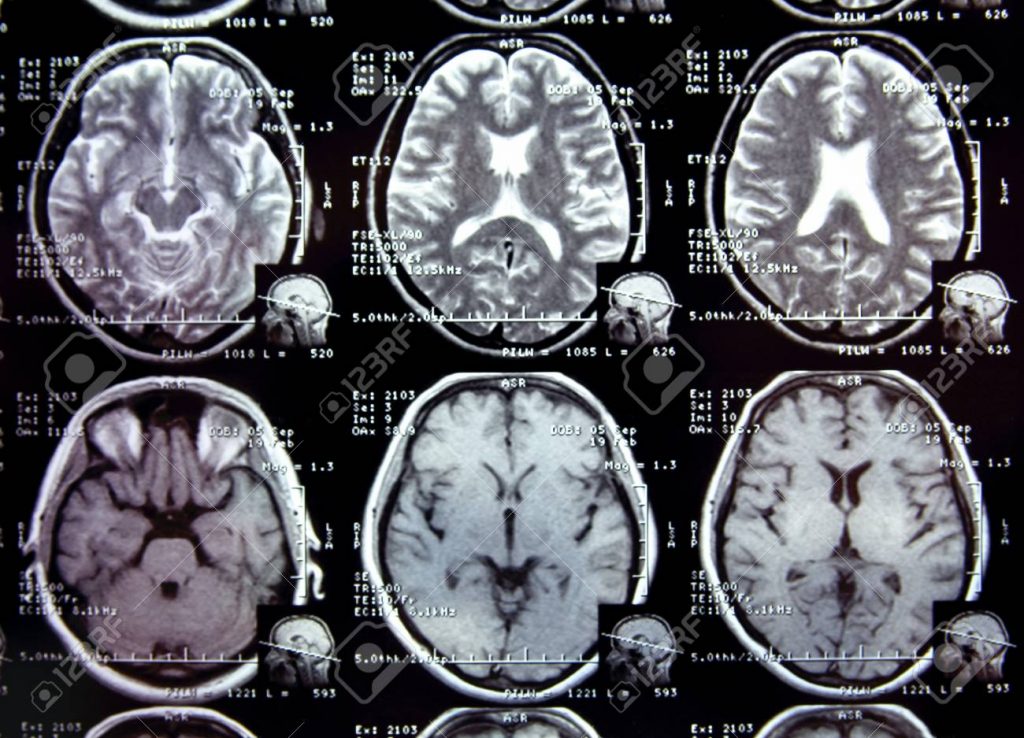

Además de los resultados de las pruebas de memoria, los científicos observaron cambios en la activación de las estructuras cerebrales con la resonancia magnética funcional y realizaron análisis de sangre para medir los niveles de endocannabinoides. Los diferentes análisis coinciden: cuanto más rápido son los individuos, más activan su hipocampo (el área cerebral de la memoria) y el núcleo caudado (una estructura cerebral implicada en los procesos motores).

Además, sus niveles de endocannabinoides siguen la misma curva: cuanto más alto es el nivel después de un esfuerzo físico intenso, más se activa el cerebro y mejor es el rendimiento del cerebro. «Estas moléculas están implicadas en la plasticidad sináptica, es decir, en la forma en que las neuronas están conectadas entre sí, y por lo tanto pueden actuar sobre la potenciación a largo plazo, el mecanismo para la consolidación óptima de la memoria», reflexiona Marín Bosch.